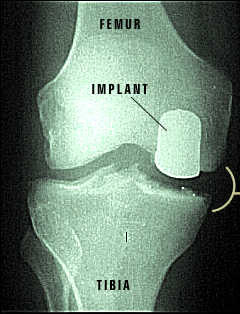

X-ray of Repaired Knee Joint

Repaired Knee

The partial knee implants have returned this knee joint to its normal functioning.  You can see the difference made by the implants when compared to the damaged knee before surgery.